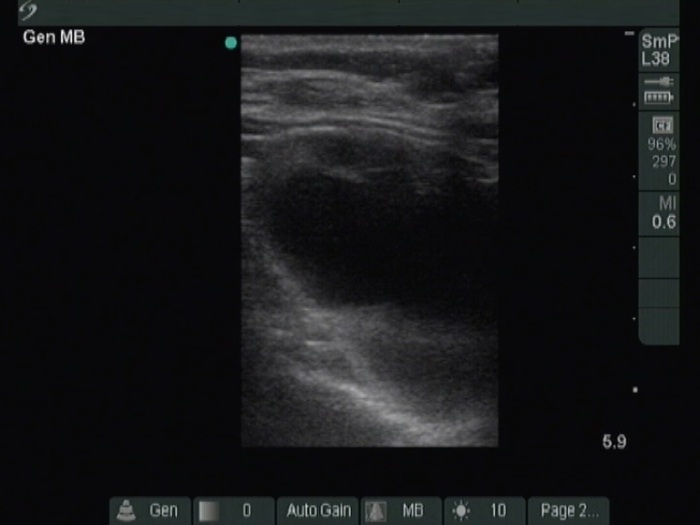

Ultrasonography. The thyroid was moderately hypoechoic. A large cystic nodule occupied great part of the right lobe. There was a moderately hypoechoic solid nodule in the lower third of the right lobe. This lesion presented with taller-than-wide and taller-than-long shape and had both perinodular and intranodular vascularity.

FNA of the solid nodule in the lower third of the right lobe resulted in oxyphilic cell tumor.

Histopathology disclosed oxyphilic variant of a minimally invasive follicular carcinoma in the suspicious nodule. The other nodules proved to be hyperplastic nodules.